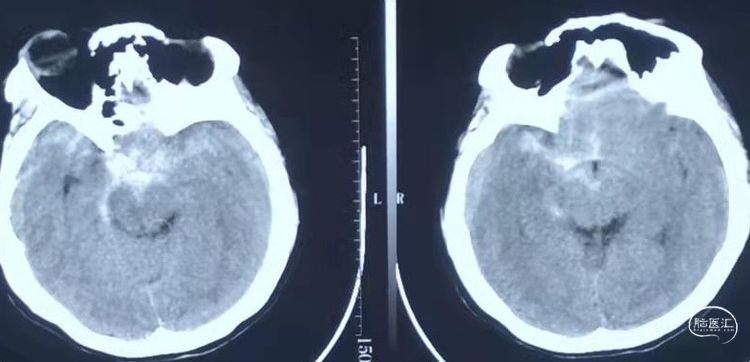

术后第一天CT。